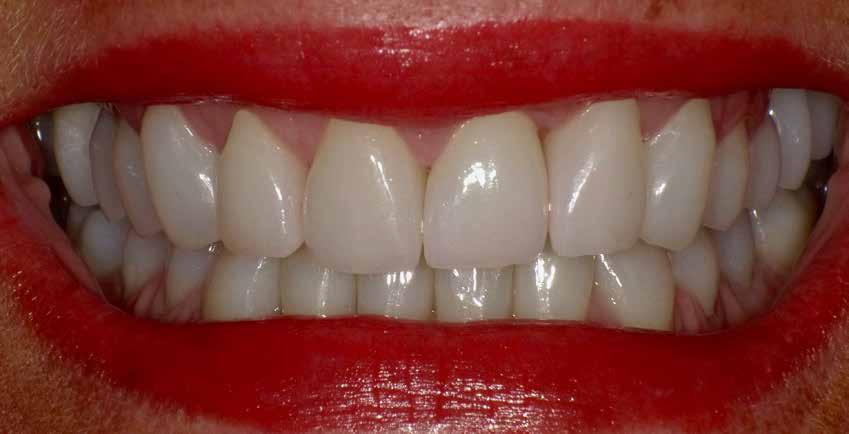

A cikkben egy fiatal nő kezelésének interdiszciplináris megközelítését foglaltuk össze, aki fogászati állapota miatt hoszszú ideje szenvedett fizikálisan és pszichésen is (1. ábra)

1. a–c ábrák: Kiindulási helyzet: fiatal páciens komoly fizikai és pszichés szenvedéssel.

A fogak extrahálása és az alveoláris plasztika teljes narkózis mellett történt meg, így teremtve ideális helyzetet a protetikai ellátáshoz. A műtéti beavatkozás után a páciens az ideglenes fogsorral távozott. Egy héttel később jött kontrollra. Nemcsak látványra változott meg nagymértékben, hanem egyértelműen magabiztosabb és önbizalommal teli volt a fellépése (12. ábra)

Az elsődleges terápiás szakasz kulcsfontosságú volt a teljes rehabilitáció szempontjából. A páciensnek nem csak szép, esztétikus mosolyt kölcsönzött, hanem életminőségének javulását is hozta (13. ábra). A Digital Denture folyamatnak köszönhetően a kezelés ráfordításai is alacsonyak voltak. A fiatal nő messzemenően boldog, magabiztos és motivált a következő lépéshez.

12. ábra: Páciensünk egy héttel fogainak extrahálása és az ideglenes fogsor azonnali behelyezése után. 13. a–d ábrák: Látványos átalakulás: kezelés előtt és után. A páciens maga hangsúlyozta ki életminőségének jelentős javulását.